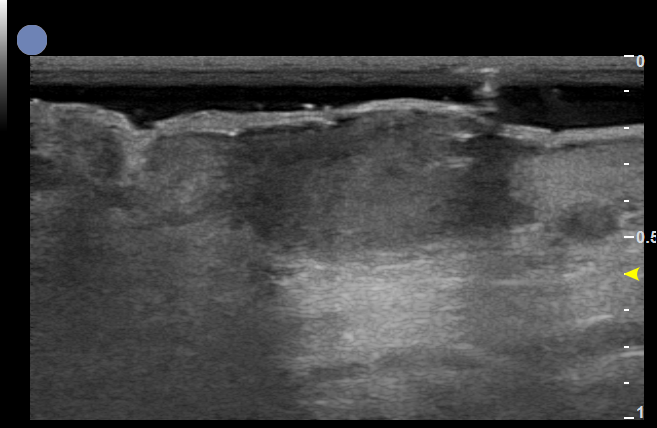

痤疮-面